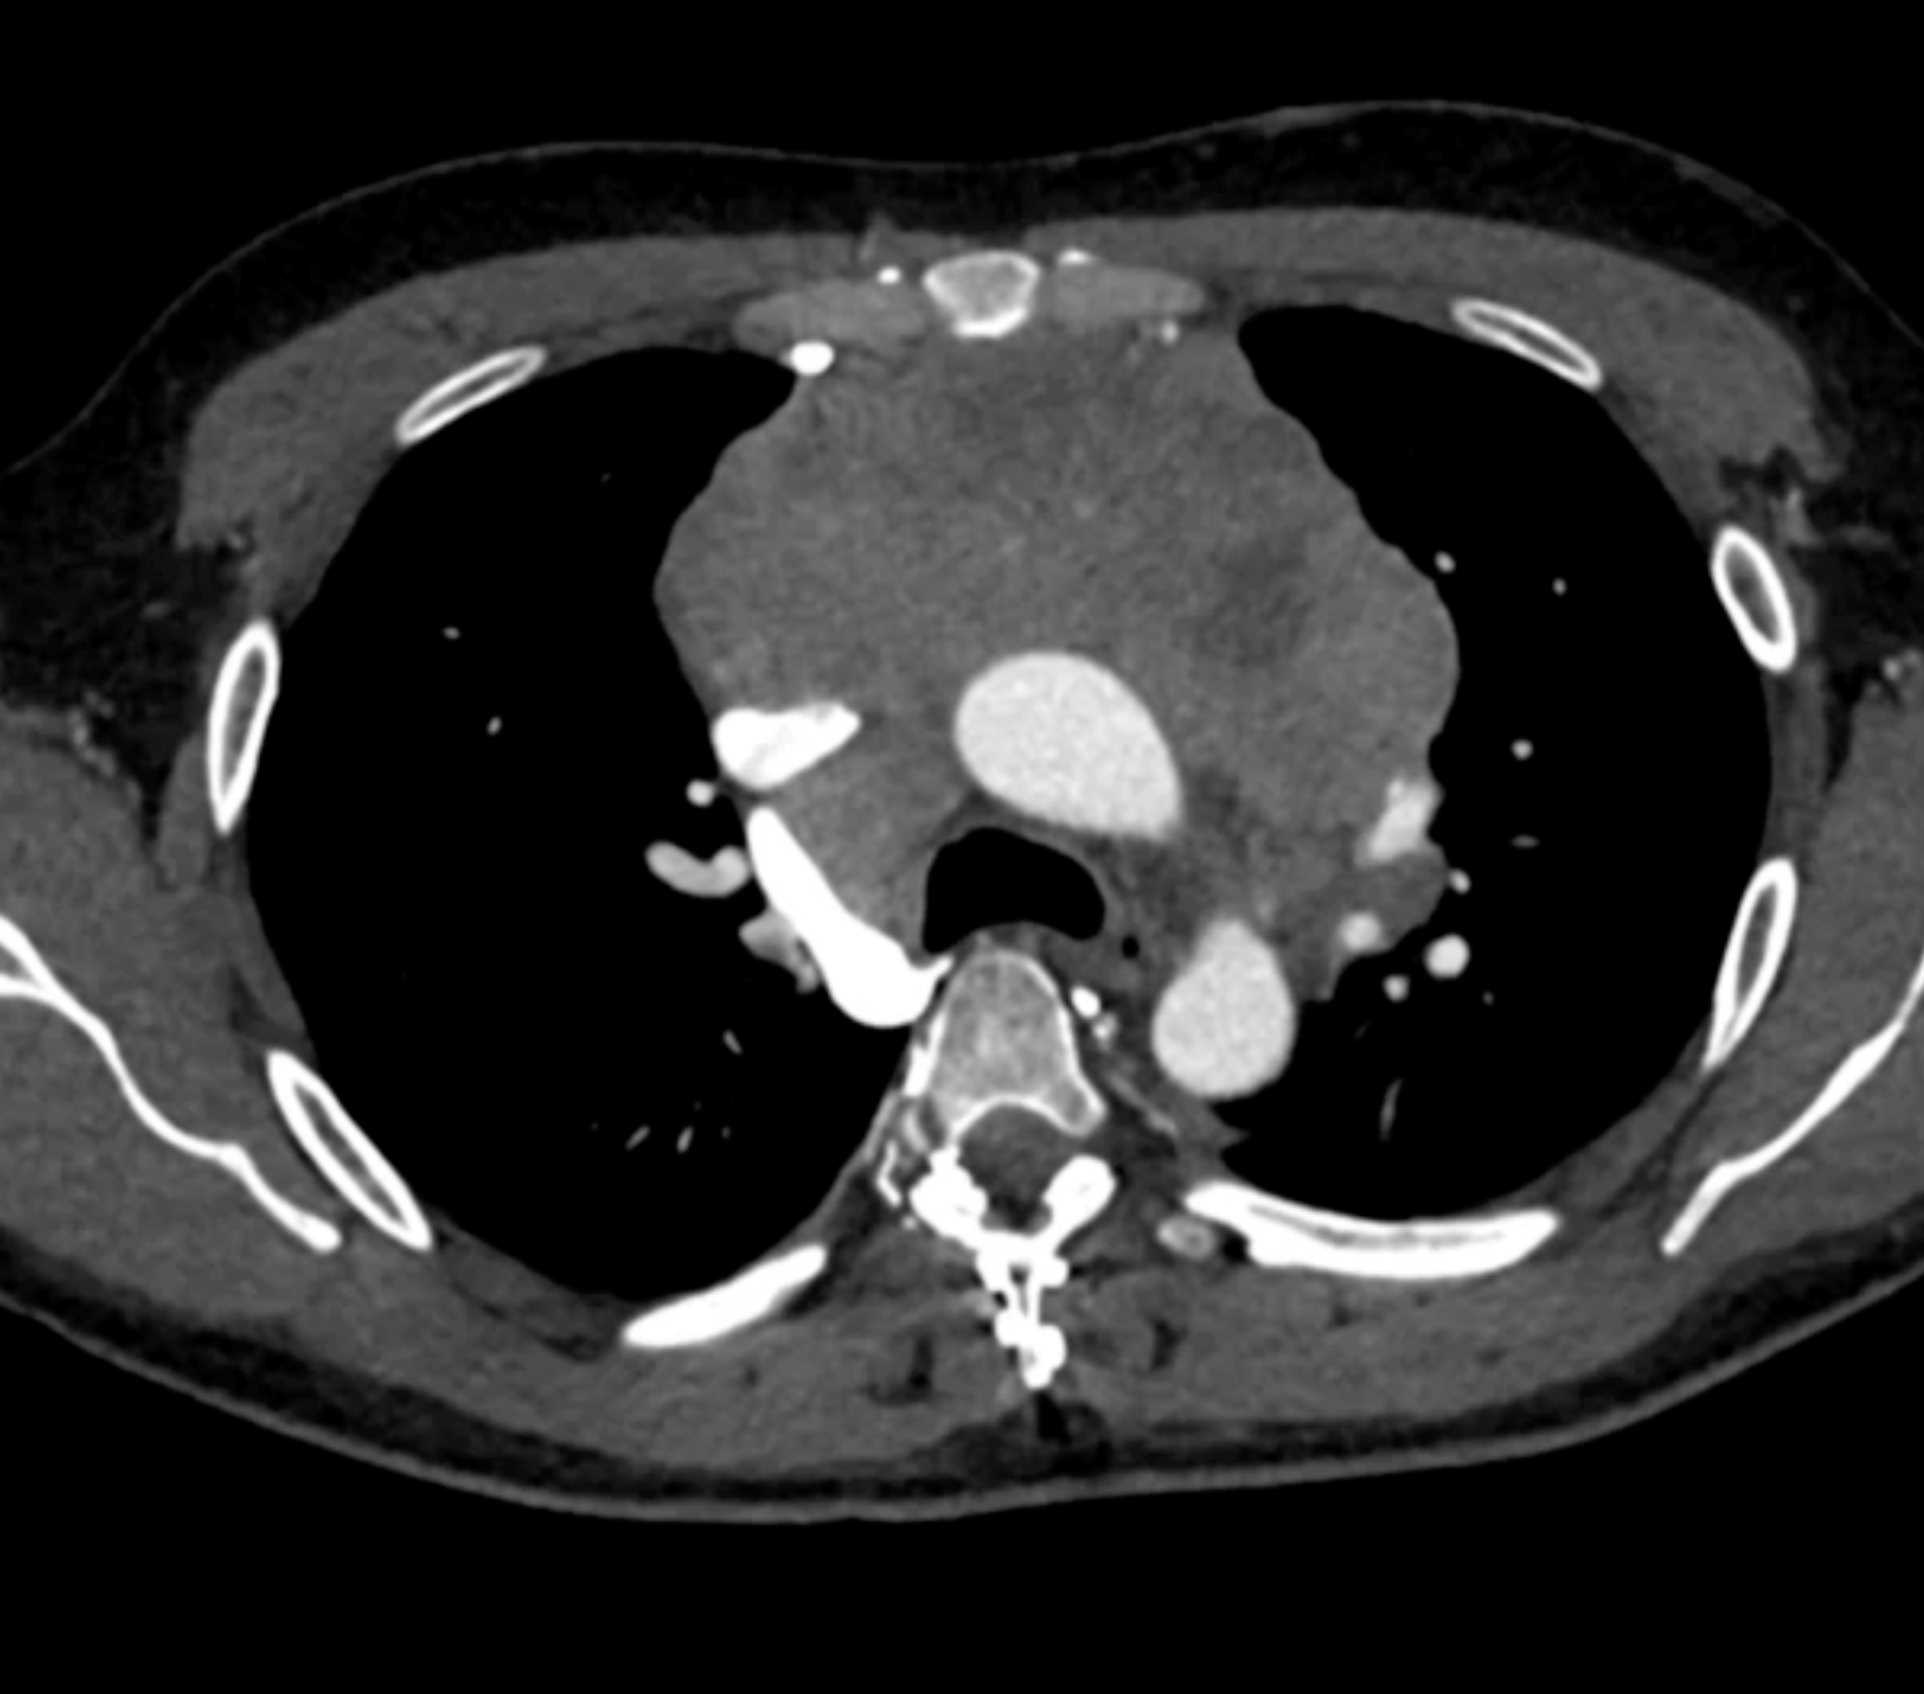

Thymic Carcinoma